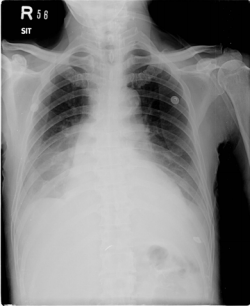

6. 下圖之胸部 X 光片,其 cardiothoracic ratio 約為多少?

(A)10.0~29.9% (B) 30.0~49.9%(C)50.0~69.9% (D)70.0~89.9%